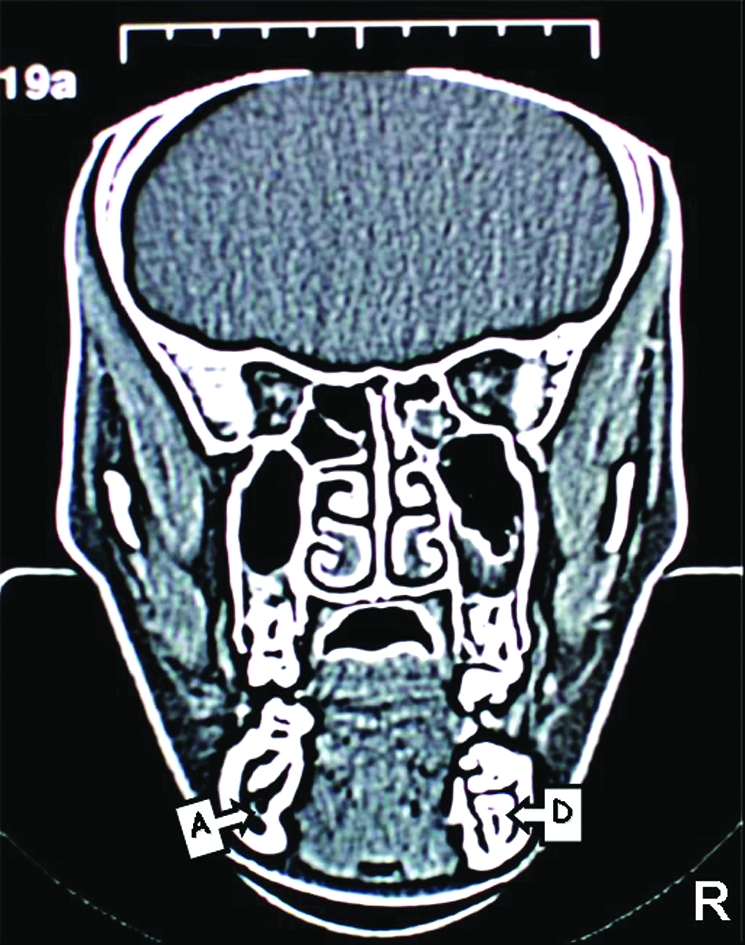

Figure 4.

CT images of the patient. The position of right inferior dental canal can be seen clearly as a dark area but left inferior dental canal cannot be seen due to the impacted second premolar. (A; Right Mandibular Canal, B; Left Mandibular Canal, C; Tipped Right First Molar, D; Impacted Right Second

In order to assess the position of the inferior alveolar canal and the relationship between the canal and second premolar a coronal, CT was taken (Philips Tomoscan, Netherlands). CT scanning of the mandible consisted of 26 slices with a thickness of 3mm and 1mm slice gap. Relationship of inferior alveolar canal and impacted premolar can be observed in Figure 4. Furthermore the amount of bone volume of the involved section and symmetrical section (to compare the bone volume) calculated from the slices on post processing screen of the system. The bone volume was 8.46cm3 on the right side compared to 12.75cm3 on the opposing side which demonstrated that the structural weakness could arise, if molar, premolar and primary second molar were extracted. This could lead to long term problems such as potential pathological fracture of the mandible.

In addition to the plain radiographies a CT was taken, due to the difficulties of locating the inferior alveolar neurovascular bundle in our case, which enabled us to determine the involved area more precisely for ensuring the vital structures are protected. The bone volume was calculated 8.46 cm3 on the right side and 12.75 cm3 on the opposing side from post processing screen of the system. This may imply extensive bone removal is required for extraction of the affected teeth which may predispose mandible to pathological fracture. Besides the possibility of eruption of second premolar was not considered in our case Premolar) as the tooth had curved root shape. Moreover, CT images revealed that mandibular nerve passes the impacted teeth in a very close proximity. Damage to the inferior alveolar nerve during the process of removal of the impacted teeth is highly likely. Previous reports documented that multiple impacted teeth were only observed with no surgical exposure or orthodontic traction due to the risk of extensive bone loss after surgical intervention.1,23